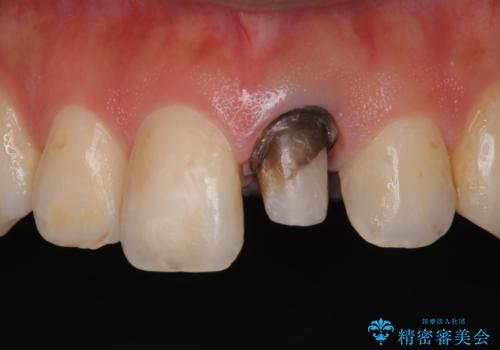

- 矯正前に仮歯にしていた前歯を矯正治療終了後にセラミックによる治療を希望された患者様です。

プラスチックのものから綺麗なセラミックになり喜んでいただきました。